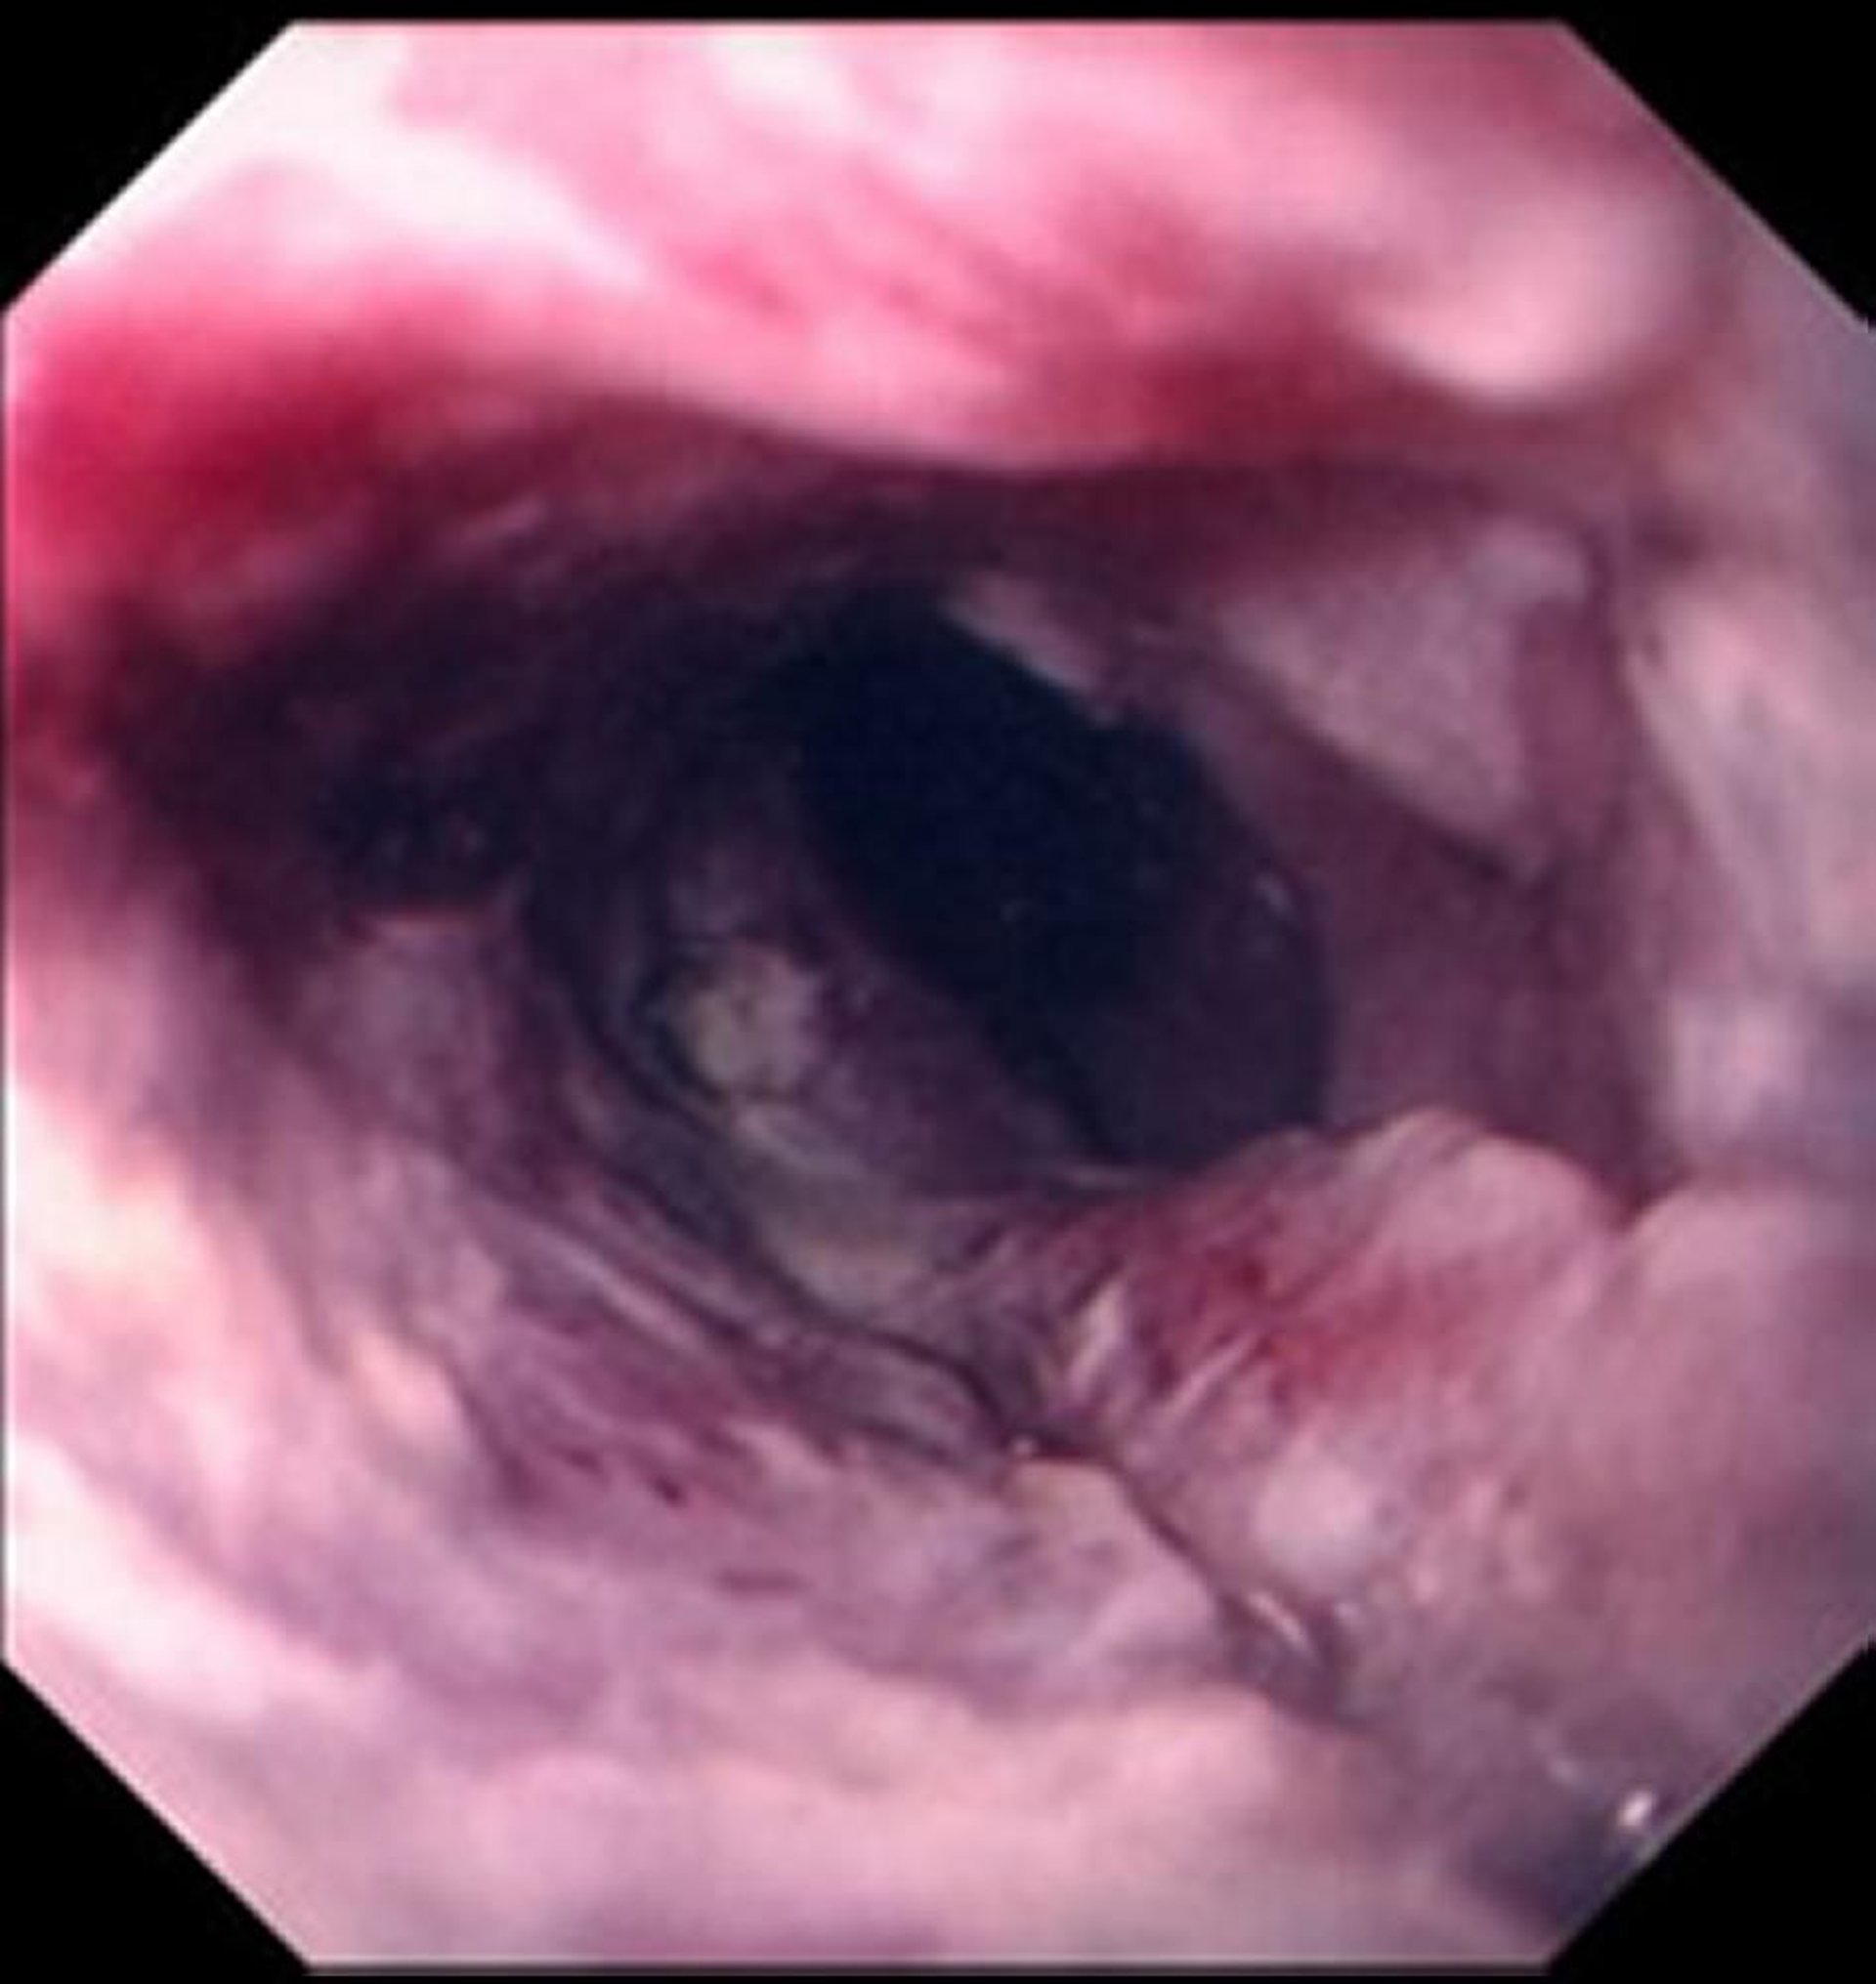

Squamous Cell Carcinoma of the Esophagus

Squamous cell carcinoma typically manifests as an ulcerated, ragged mass compromising the lumen of the esophagus.

Images provided by David M. Martin, MD.